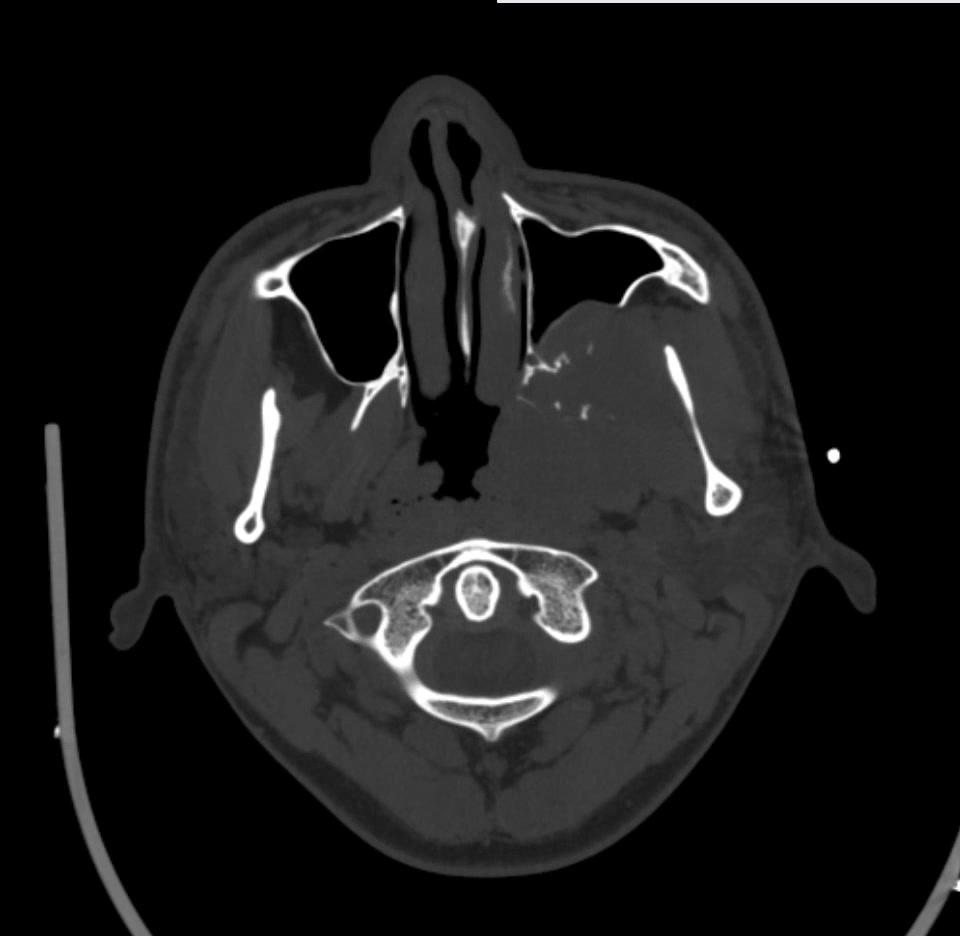

简要病史:左眼视力下降20余天,伴肿胀疼痛不适半月

CT平扫: